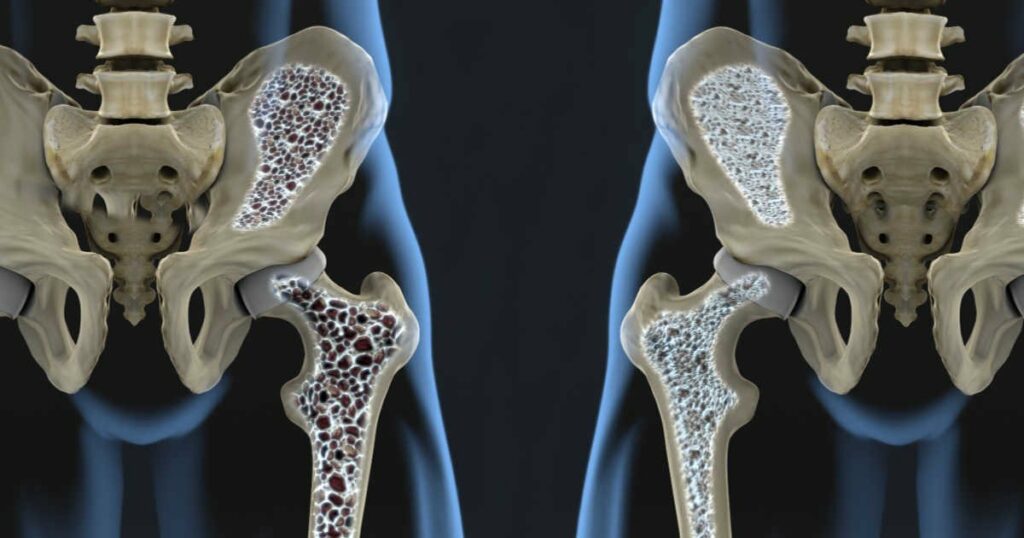

A Organização Mundial da Saúde (OMS) estima que o número de casos de osteoporose deve crescer três vezes até 2050, alcançando aproximadamente 6,3 milhões de novos diagnósticos por ano em todo o mundo. No Brasil, de acordo com dados do Ministério da Saúde, 10 milhões de brasileiros são afetados pela doença atualmente.

“Osteoporose é a perda acelerada de massa óssea, que ocorre no envelhecimento, e provoca a diminuição da absorção de minerais e de cálcio. A doença é caracterizada pela fraqueza dos ossos que, na maior parte das vezes, só é diagnosticada após a ocorrência de fraturas e deformidades”, explica a endocrinologista Erica Barcellos.